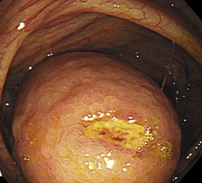

Κολονοσκόπηση που αποκαλύπτει πολυποειδή μάζα που προβάλλει στο μέσο τμήμα της αριστερής κολικής καμπής